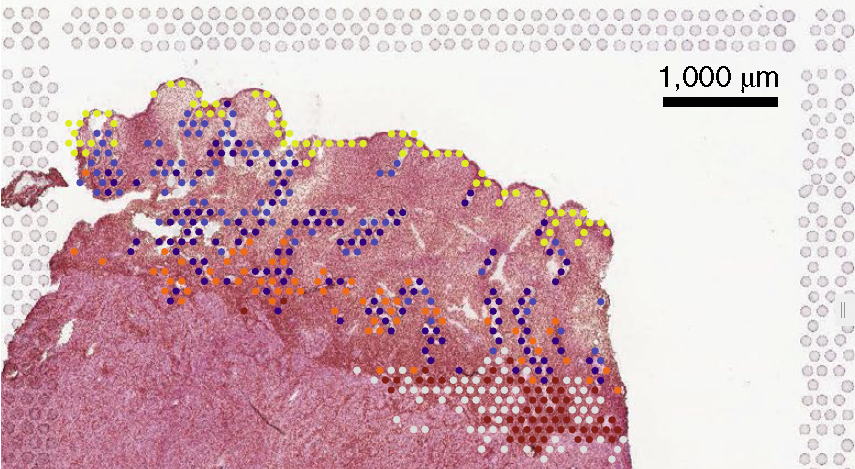

该文报道的人类子宫细胞时空图谱有两大新突破:其一是对移植供者的子宫细胞的图谱分析,生成了一个全面的子宫细胞主要亚群目录,涵盖子宫内膜和肌层的细胞定位,这是常规子宫内膜活检所没有的。研究者还将该数据集与另一个最近的子宫内膜活检单细胞图谱数据集整合,揭示了包括仅限于基底层的成纤维细胞(成纤维细胞C7)等等其它细胞状态,大大提高了功能性子宫内膜层的时间分辨率。其二, 研究者用10x Genomics Visium和定量多重smFISH技术进行空间定位的策略,确定了细胞分离物转录组分析中描述的三维细胞排列,并通过反褶积方法将细胞映射到组织中,例如将上皮细胞分配到三个主要的子宫内膜层:内腔层、功能层和基底层。研究团队还开发了CellPhoneDB v.3.0系统,融入细胞的空间坐标来检测细胞间的通讯,并用它定义内腔上皮和腺上皮微环境的细胞信号传导(开源Web服务器可从www.reproductivecellatlas.org获得)。

该文在方法学上特别指出“空间转录组学技术的爆发提供了结合细胞相互作用来解析组织结构的独特机会”。细胞的空间排列是理解复杂组织形态的关键, 比如子宫内膜细胞的功能可能会因接收到邻近细胞的信号而不同。通过单细胞和空间转录图谱,该文分析了育龄妇女月经周期增殖及分泌阶段子宫内膜细胞的状态和空间定位,绘制了单细胞分辨率的三维子宫内膜类器官图谱研究其体外激素反应特征,并设计了一种计算工具包与体内观察结果比较,对该模型系统进行校准。最后, 通过调节类器官培养物中WNT和NOTCH通路,调节子宫内膜谱系特异性上皮细胞,定义卵巢激素反应相关的分子事件。整个工作结合了时间和空间信息,体内和体外的数据,为今后组织工程实验充分利用人类细胞图谱(Human Cell Atlas)数据提供了参考范本。